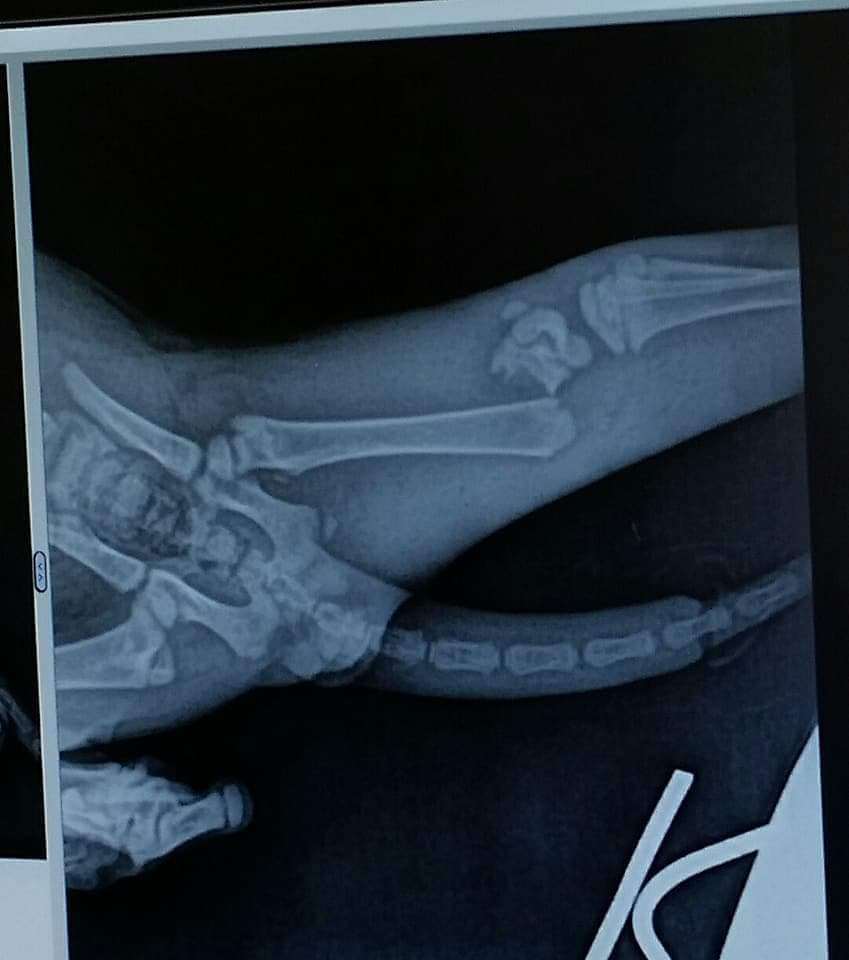

Let me introduce you to the amazing Miracle! This lovely soul has been through the wringer but still shines like the brightest star in the sky! ⭐️ Born on April 4th, 2018, Miracle is a true warrior who's had three major surgeries to save his little body, including a heroic move to become a bobtail. Can you believe that? Talk about resilience and strength! 💪 Imagine being just a kitten and facing such challenges. Miracle was rescued from a most unfortunate situation, having been hit by a car and then found by a kind-hearted good Samaritan named Deb. As if that wasn't enough, he was also left with a severely injured rear leg and a dying tail. 😢 But his luck changed when he was brought to a loving vet who vowed to give Miracle the care he so deserved. This sweet boy has already finished his kitten vaccinations, is FIV and FeLV negative, has been dewormed, is on flea prevention, and he's neutered! Now, although Miracle is officially an adult, he still has that delightful spirit of a playful kitten, and he’s just bursting with joy, love, and sweetness! 🥰 He’s looking for a special home that can appreciate his brave little heart and provide him the love he needs. Plus, a yummy diet of CD canned food is essential for him to thrive! Miracle’s journey hasn’t been easy, but with your support, he can continue to heal and flourish. 💖 Miracle House Animal Rescue is devoted to giving loving animals like Miracle a second chance. Located just east of Cincinnati, Ohio, they work by appointment only once you’re approved to adopt. If your heart is open and you think you can provide a nurturing environment for this precious baby, you can bookmark Miracle in the Buddy App to check back in as he continues to grow and heal. Don’t wait—apply through the Buddy App to make Miracle a part of your family! 🌈